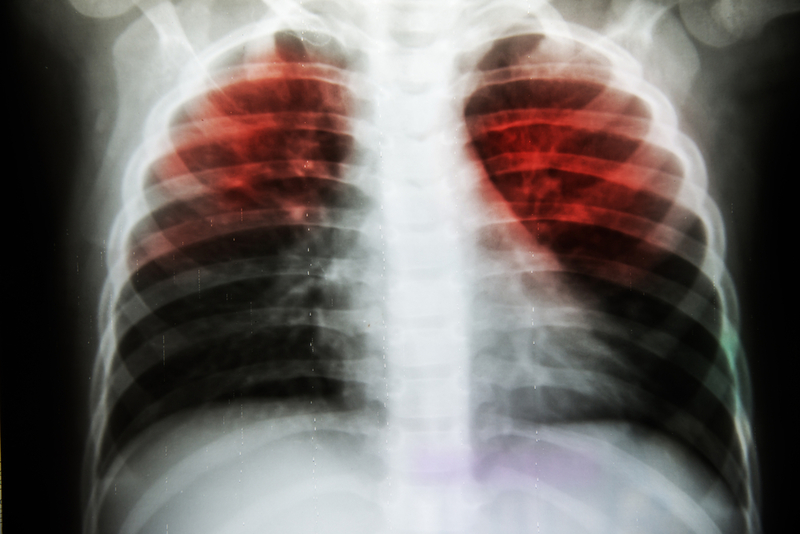

Government claims be damned, tuberculosis rages in UP

Tuberculosis continues to affect a sizeable population in Uttar Pradesh, particularly in rural areas, despite tall claims by the Centre and the state government about improvements in public health and free healthcare.

In 2018, over 4.2 lakh TB patients were notified in Uttar Pradesh, the highest in the country. Between 1 January and 15 March this year alone, over 68,000 people have been notified in the state. However, state Governor Anandiben Patel and the Raj Bhawan staff's decision on Monday to adopt 22 children suffering from tuberculosis from areas around her residence, has suddenly turned the spotlight on to the enormity of the disease right here in the state capital.